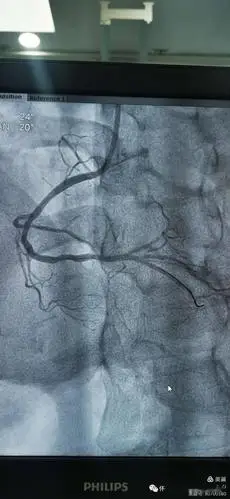

【特别关注】怀仁市人民医院介入导管室完成冠脉造影11例,支架植入2例